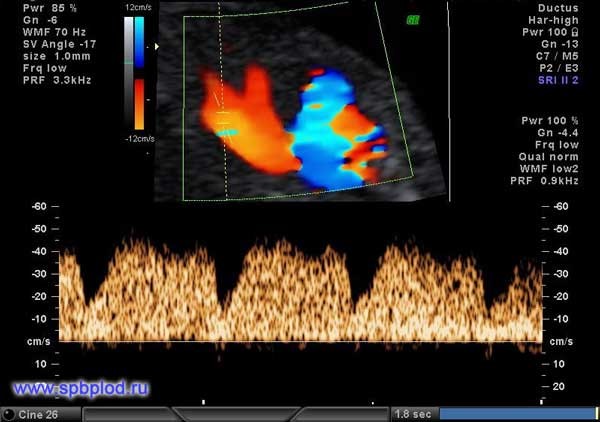

Помимо измерения толщины воротникового пространства и оценки носовой кости, предложено еще несколько маркеров: оценка кровотока через трикуспидальный клапан сердца и через венозный проток, а так же измерение лицевого угла плода. Оценка данных маркеров требует от врача высокой квалификации, и возможна только после получения международной сертификации по каждому маркеру.

Обычно кровь в сосудах плода течет в одном направлении: от сердца к периферическим сосудам. При наличии хромосомной патологии у плода или пороков сердца направление тока крови может изменяться, и в некоторые фазы сердечного цикла кровь начинает течь обратно к сердцу.

Нормальный кровоток через трикуспидальный клапан сердца плода при сроке 12 недель